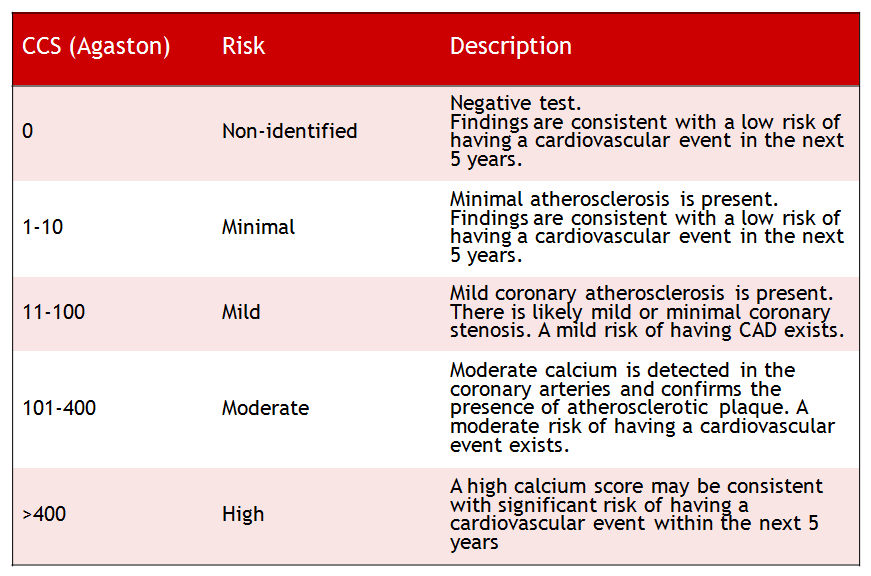

Scoring coronary artery calcium cac tab bmj 1620. Coronary artery calcium scoring. Calcium score jama coronary artery